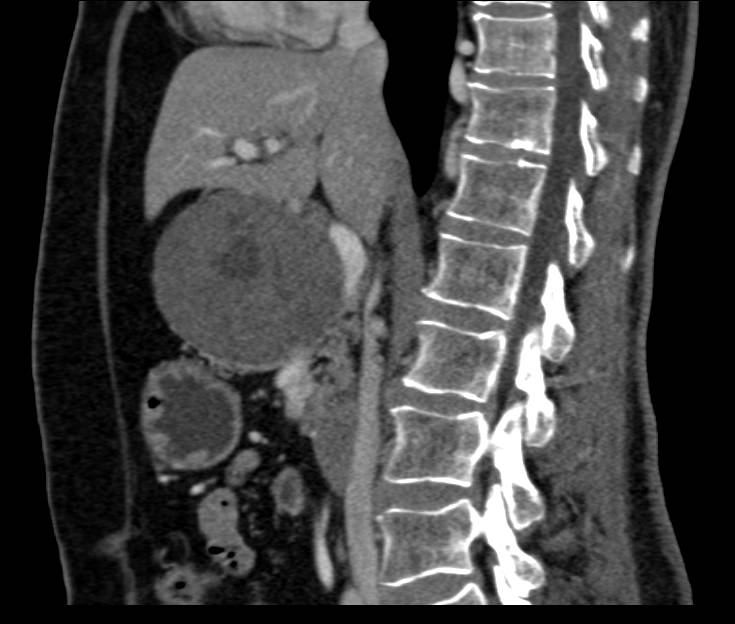

Pancreatic Neuroendocrine Tumor (PNET) Pancreas was an Insulinoma